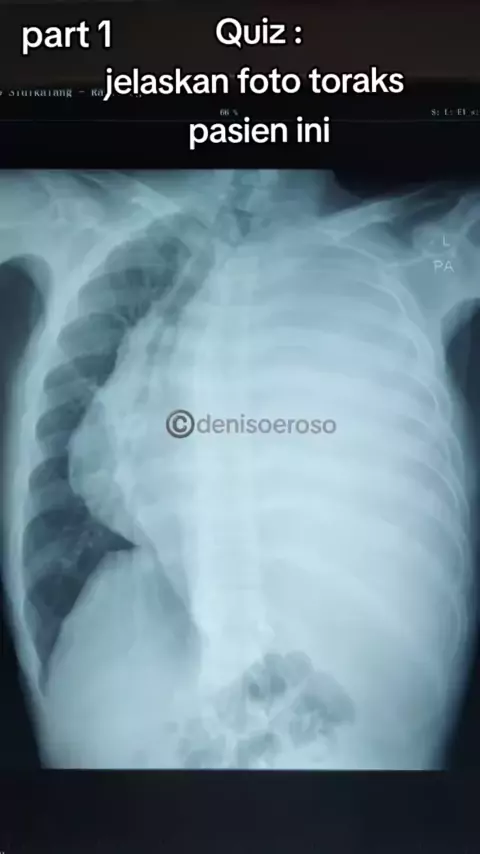

Quiz : tolong anda jelaskan gambaran apa pada foto toraks ini, pemeriksaan apa yang paling penting utk tegakkan diagnosa pasien ini#radiologi#lung#fototoraks#chestxray#dokterviral#spesialisparu#spesialisparumedan#dokterparu#dokterparuparu##p゚